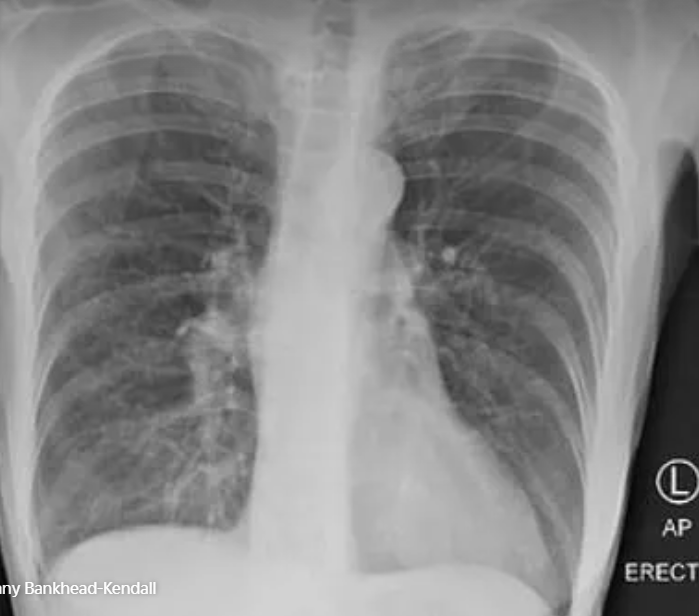

Theo thứ tự, ảnh đầu tiên là phổi của người khỏe mạnh bình thường, ảnh thứ 2 là phổi của người hút thuốc và cuối cùng là phổi của bệnh nhân Covid-19. Có thể thấy lá phổi trong ảnh đầu tiên sẫm màu và không có vết tích lạ, ảnh thứ 2 có sẹo, còn phổi trong ảnh thứ 3 lại mờ đục vì chất nhầy.

Lá phổi của người nghiện thuốc lá.

Lá phổi bệnh nhân Covid-19.

Các bác sĩ trước đây đã cảnh báo về tác động của “Covid kéo dài”, tức các triệu chứng mà người mắc Covid-19 gặp phải dù đã khỏi bệnh, bao gồm mệt mỏi, khó thở, tim đập mạnh, đau khớp, đau cơ và “não sương mù”. Theo Bankhead-Kendall, trong số những người mà cô đang điều trị, tất cả bệnh nhân từng trải qua các triệu chứng đó đều có lá phổi bị tổn thương nặng nề trên kết quả chụp X-quang.

Đáng sợ hơn, ngay cả những người không có triệu chứng cũng có thể gặp tình trạng tương tự. “Vẫn có những người nói: 'Tôi ổn, tôi không có vấn đề gì cả'. Nhưng kết quả chụp X-quang phổi của họ đã chứng minh điều ngược lại”, cô nói.